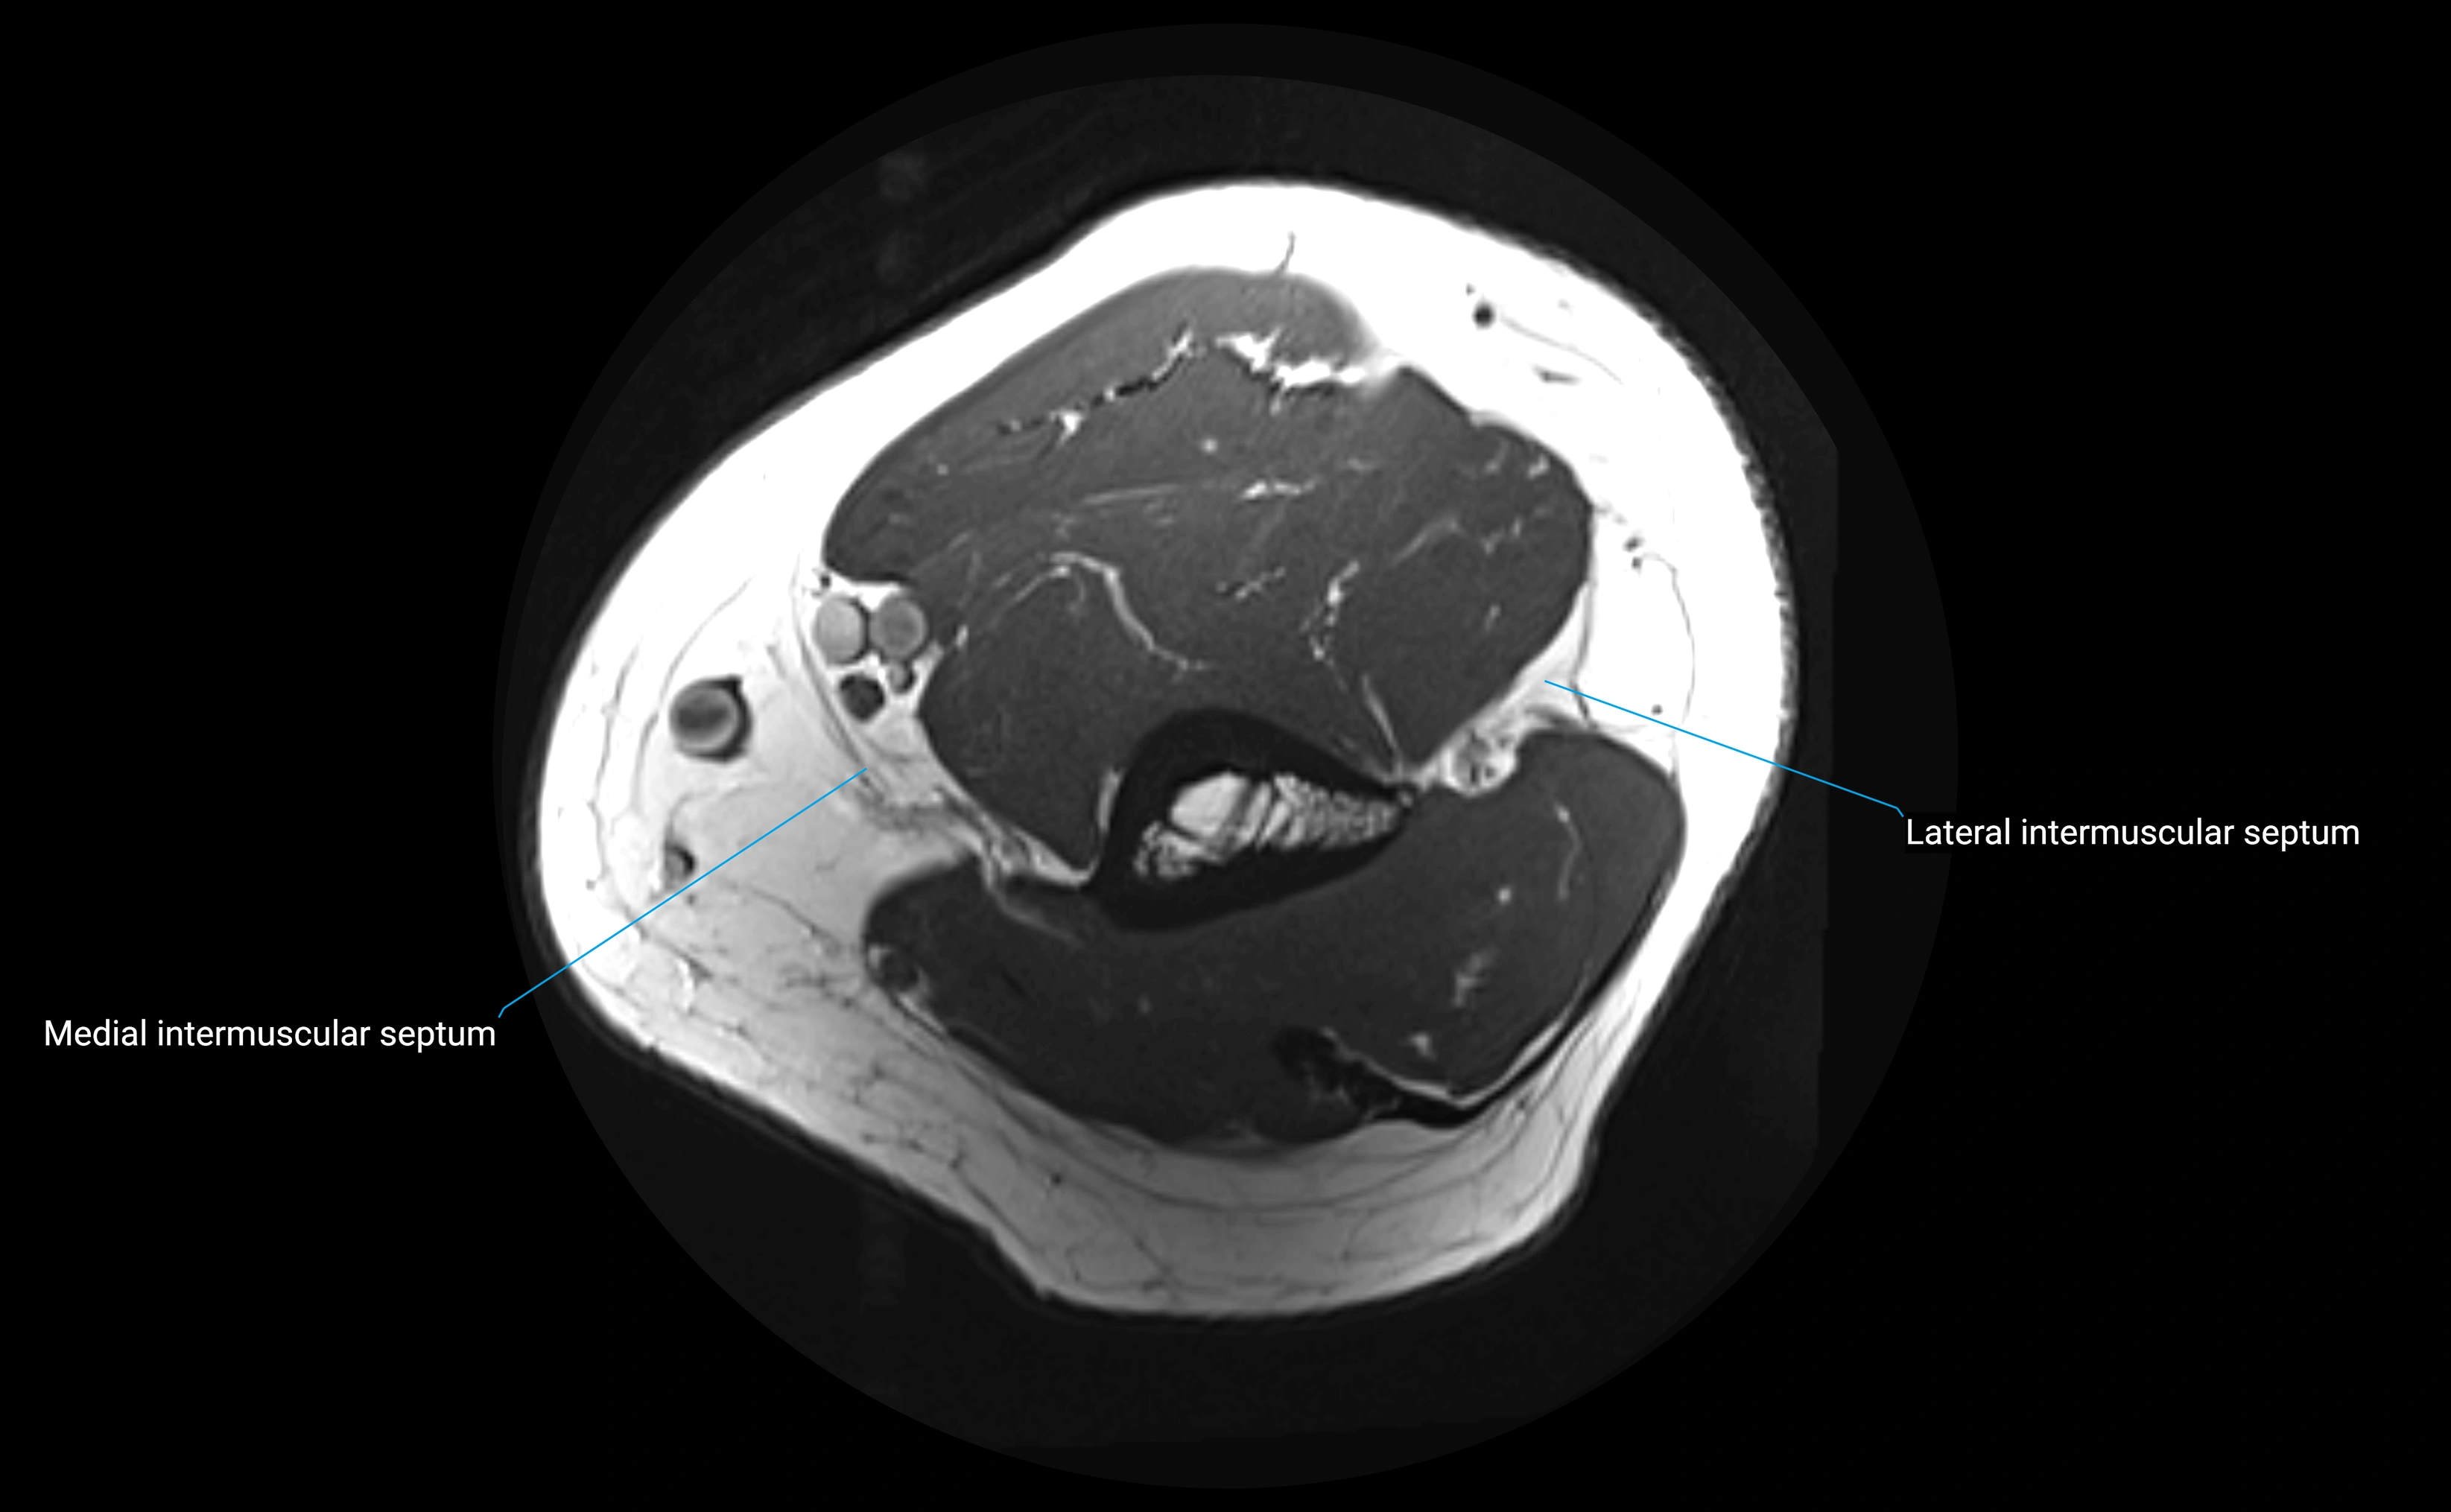

MRI images

image